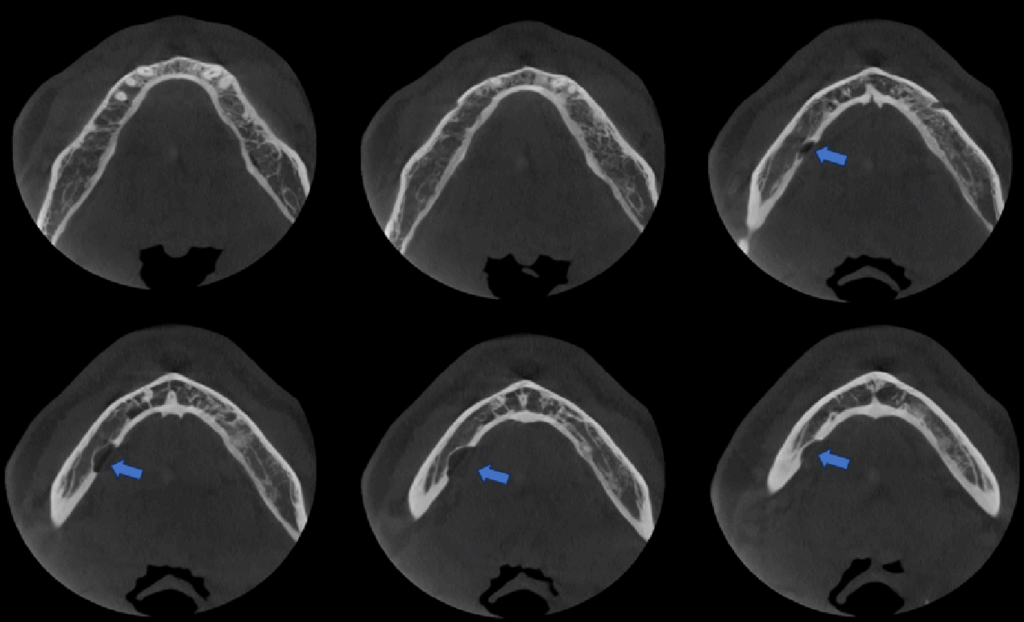

A la evaluación de la tomografía computarizada de campo mediano se observa en cortes axiales la misma imagen efectivamente parcialmente corticalizada, y que ocasiona la perdida de continuidad sólo de la tabal ósea lingual, a pesar de que en los cortes tangenciales de vestibular a lingual se asemejaría a la forma de una lesión quística en formación que se encuentra en contacto con el reborde basal, también notamos que respeta la cortical del conducto dentario inferior, finalmente en los cortes transaxiales y en la reconstrucción 3D podemos tener una mejor visión de la cavidad que no posee características patologícas y las estructuras óseas y dentarias adyacentes que no presentan alteración aparente.

CORTES AXIALES